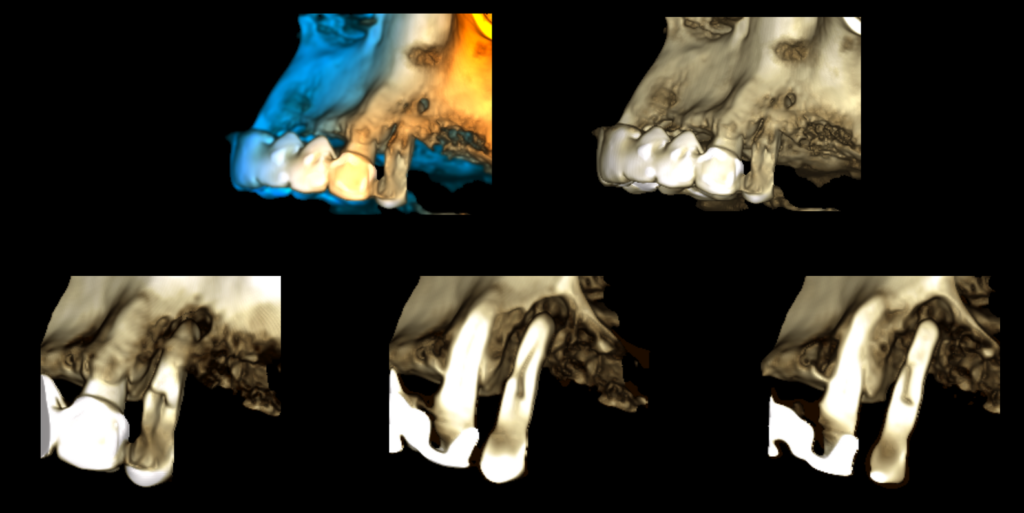

En la reconstrucción tridimensional (3D) se evidenció con mayor claridad el trazo de fractura radicular diagonal correspondiente a la pieza 24 (Figura 5).

RECONSTRUCCIÓN 3D